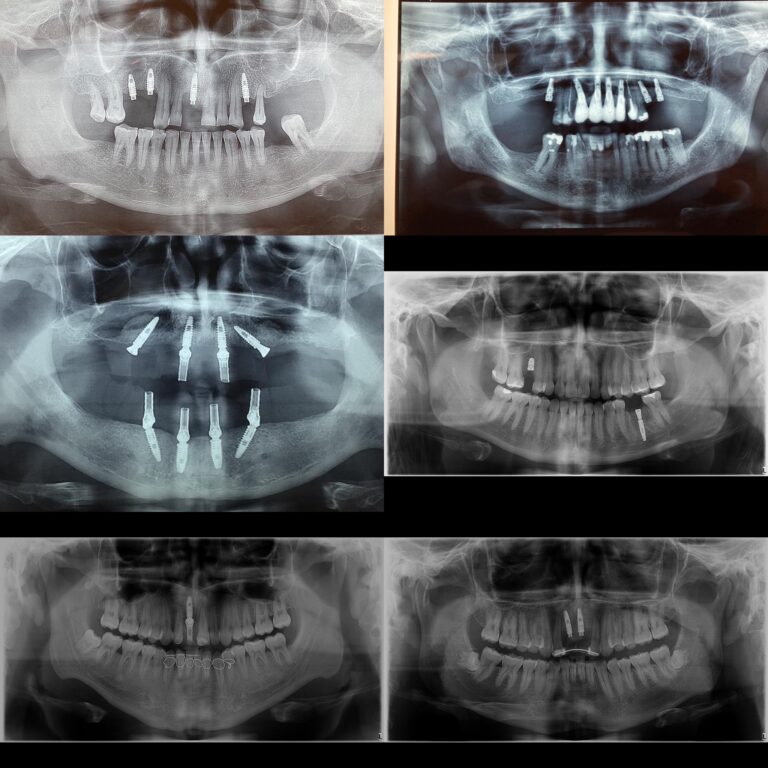

Implantes Cigomáticos y Mandibulares “all on four”

Los implantes cigomáticos son una alternativa a los implantes dentales convencionales para pacientes...

Implantes dentarios

Los implantes dentarios son una opción de tratamiento utilizada para reemplazar dientes perdidos o...

Implantes dentarios, injerto de hueso y Rehabilitación fija

Los implantes dentales, el injerto de hueso y la rehabilitación fija son procedimientos dentales que...